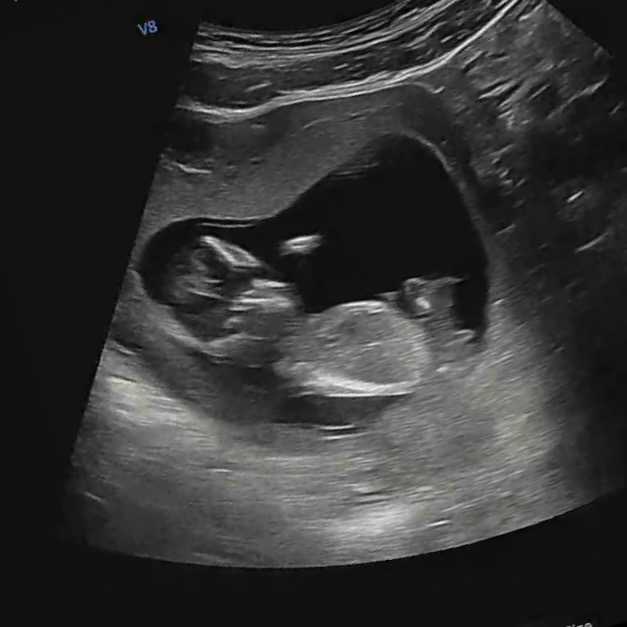

13주 1일차 각도법 봐주실분..!

실제 12주5일차인데, 초음파상 13주1일차로 나왔어요. 각도법 보는법이 감이 안오네요.. 전혀 모르겠어요ㅠㅠ

딸 같아요!